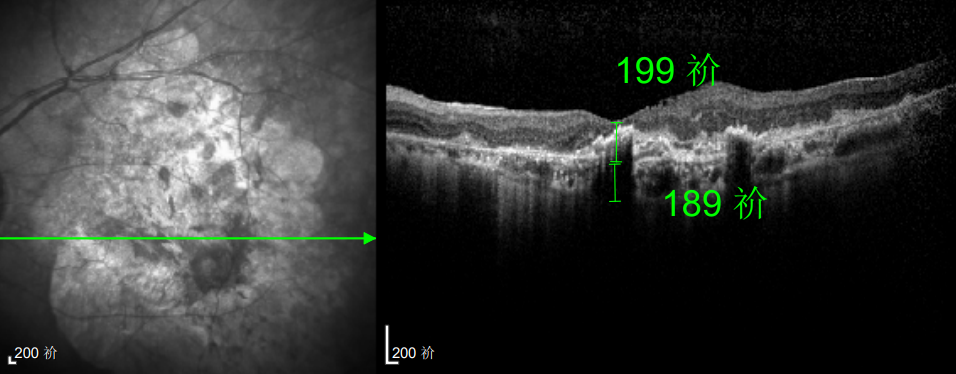

△延誤復(fù)查后的左眼

這次教訓(xùn)讓林婆婆徹底醒悟,此后她嚴(yán)格遵照王曉波主任的醫(yī)囑,定期隨訪、規(guī)范治療,再也不敢有絲毫懈怠。雖然左眼視力最終僅恢復(fù)至0.3,但穩(wěn)定的視力狀態(tài)讓她格外珍惜。